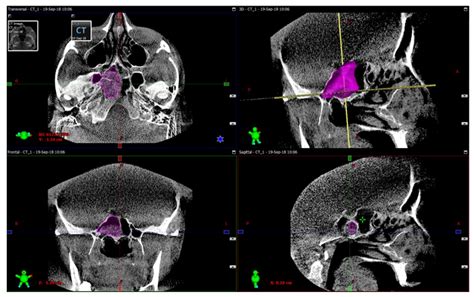

• Imaging Tests: CT scans or MRI scans to visualize the sphenoid sinuses and surrounding structures. These tests can help identify any abnormalities, blockages, or infections.

• Surgery: In severe cases, surgical procedures such as endoscopic sinus surgery may be necessary to remove blockages, correct anatomical abnormalities, or drain infected sinuses.